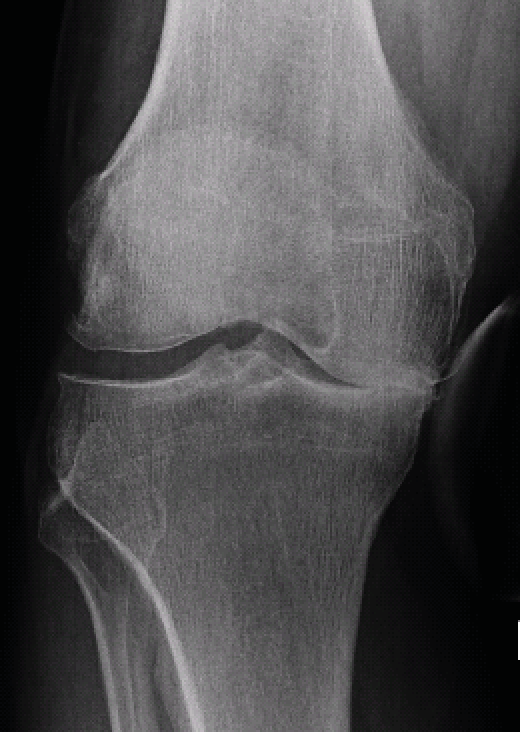

Radiographic analysis requires a weight-bearing full leg and lateral knee joint x-ray and a standard axial image of the patella. In addition, the extent of the narrowing of the joint space in the affected joint compartment should be assessed with a Rosenberg view (p.a. radiograph with weight-bearing and 45 degrees of flexion) or stress x-rays with varus/valgus stress. Since large numbers of unicondylar knee replacements are performed in our hospital, stress radiographs are standard for any unicompartmental OA requiring surgical treatment. The extent of the joint collapse and the stability of the joint can be diagnosed by these radiographs (Fig. 6, 7).